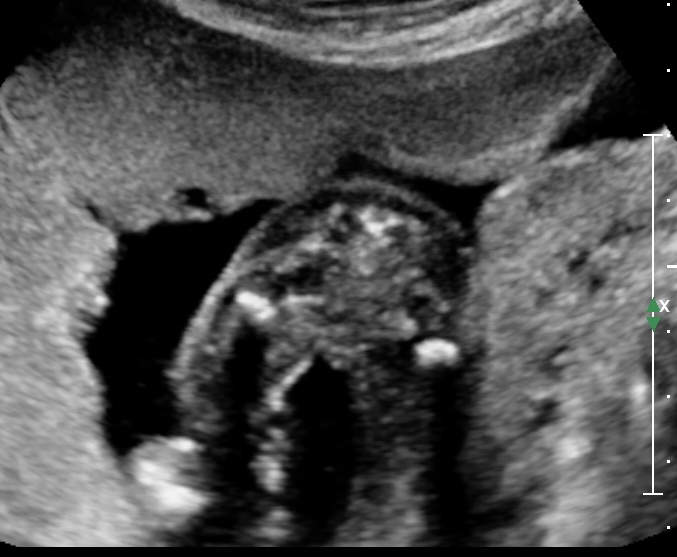

I can't be sure from the last ultrasound done at 19 weeks. There are no lines but no boy stuff either. We swayed really hard due to the fact that we already have 2 of one gender. This is our last try and I migt be living in false hope but opinions would be great! thanks!